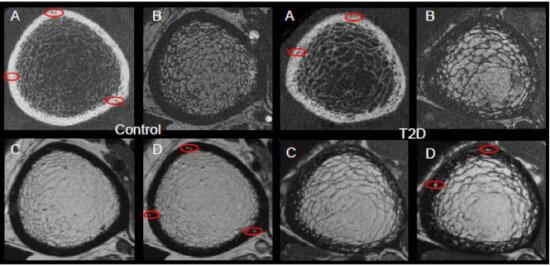

Comparison of (A)HR-pQCT, (B)fat-sensitive MR, (C)pre-contrast MR, and (D)post-contrast MR for a healthy control subject displaying exclusively vessel-filled pores (LEFT) and a T2D subject with both marrow- and vessel-filled pores (RIGHT). Prominent vessels in the post-contrast scans are highlighted in red.